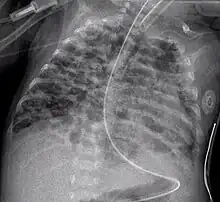

A chest X-ray showing a very prominent wedge-shape area of airspace consolidation in the right lung characteristic of acute bacterial lobar pneumonia.

Consolidation

• The air bronchogram sign, where branching radiolucent columns of air corresponding to bronchi is seen, usually indicates air-space (alveolar) disease, as from blood, pus, mucus, cells, protein surrounding the air bronchograms. This is seen in Respiratory distress syndrome[9]